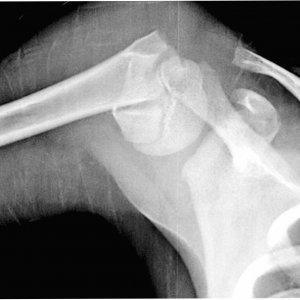

Повреждение большого бугорка чаще всего происходит по отрывному типу и сопровождается вывихом.

Это связано с прикреплением мышц, отвечающих за движение плеча.

К основным признакам отрыва большого бугорка можно отнести:

- Боль в области плечевого сустава.

- Невозможность отводить плечо назад, ограничение подвижности руки.

- Явно выраженный отек в зоне повреждения.